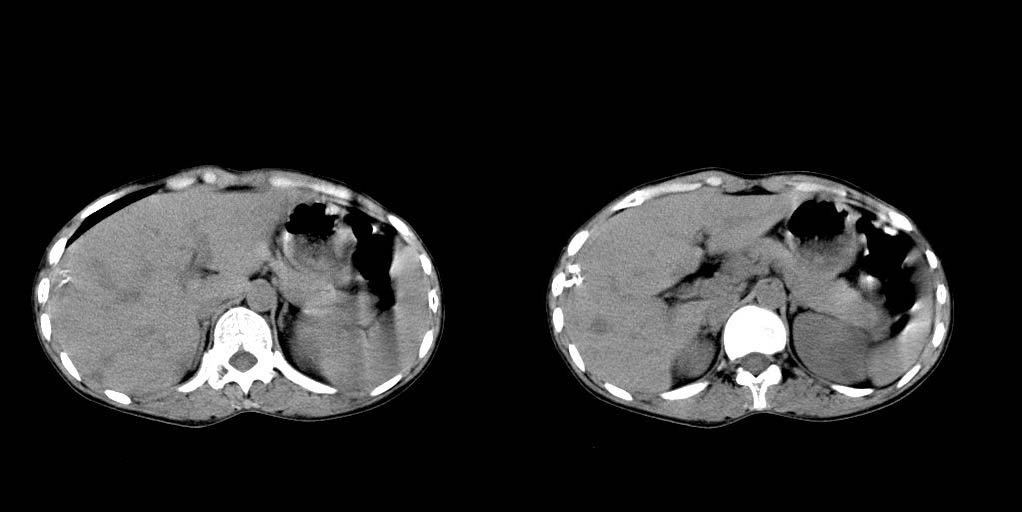

病人资料:女 30岁 右上腹部疼6天余.无其他不适,我院血常规正常,胸片正常,b超示1,肝内多发性结石.2,肝实质内似见结节影,占位病变待定.

考虑:1、肝右叶前段包膜下钙化灶;

2、肝胆胰脾ct平扫未见明显异常肿块影。

肝右叶小圆形低密度影,建议增强扫描

建议增强检查,平扫也显示脾肿大。

可能是小血管瘤 做个增强吧

肝右叶前段包膜下钙化灶;做ct增强或mri。